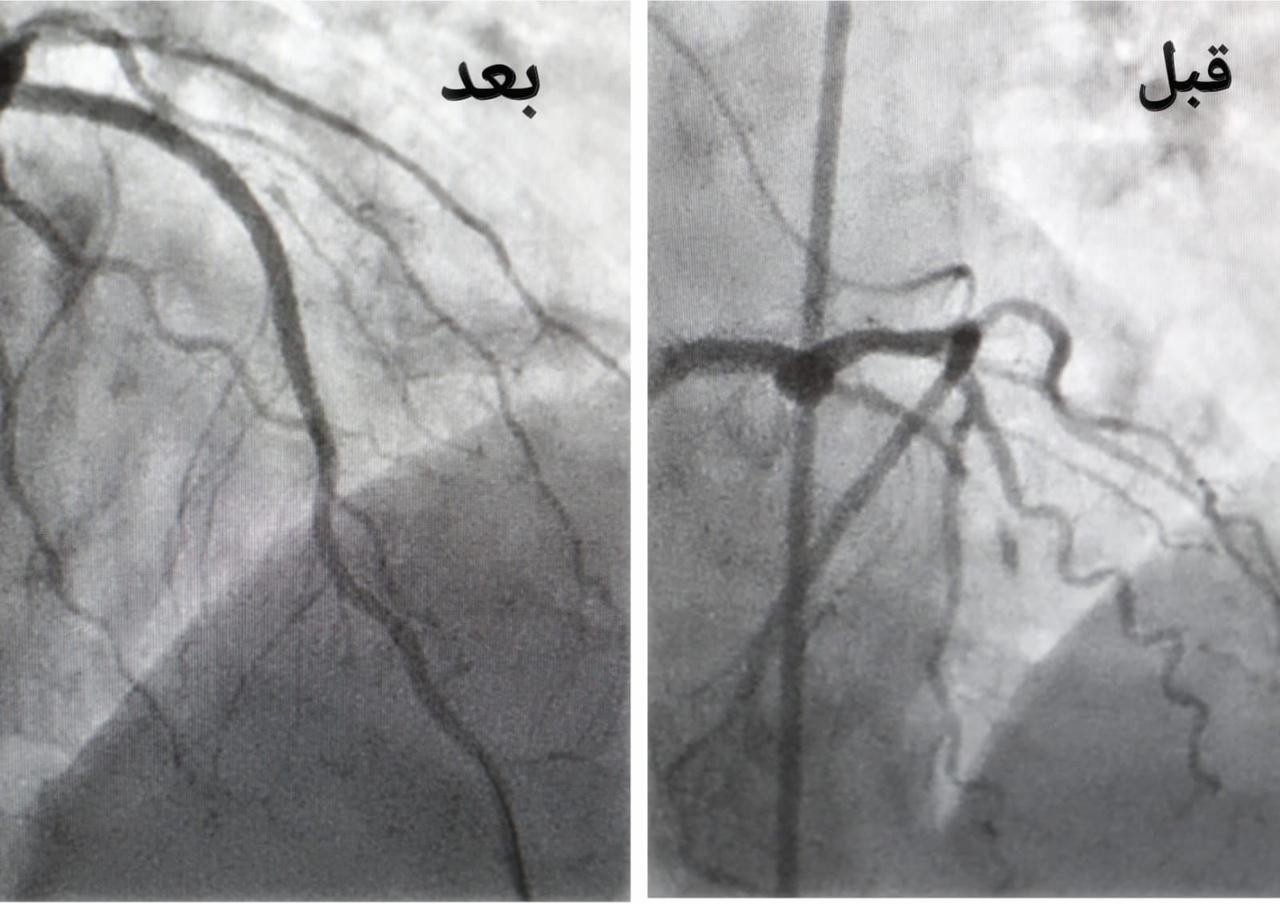

وأكدت الصحة في جدة أن الفرق الطبية بمجمع الملك عبدالله الطبي تمكنوا بفضل الله من إنقاذ حياة الحاجة حيث تعرضت لذبحة صدرية غير مستقرة و جلطة قلبية حادة، كادت أن تودي بحياتها بعد انتهاء مناسك الحج وأثناء مغادرتها المملكة، حيث أحضرت إلى قسم الطوارئ وتم تقديم الخدمات الإسعافيه الأولية لها و نظراً لوضع حالتها الصحية الحرجة نقلت على الفور إلى غرفة العمليات لعمل القسطرة القلبية العاجلة، وتم فيها فتح الشريان الأمامي النازل و تركيب دعامات دوائية في أقل من 70 دقيقة من وصولها للمجمع الطبي ليتم نقلها لقسم العناية المركزة ومتابعة الحالة لحين استقرارها وخروجها من المستشفى ومغادرتها المملكة.